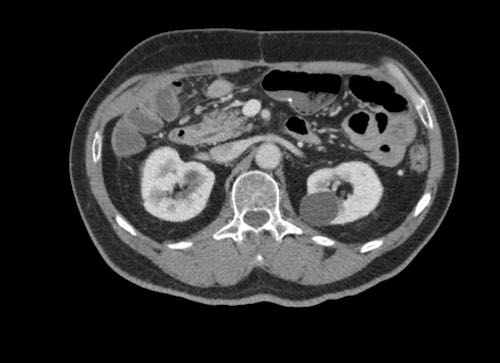

Cuộn xem ảnh CT

Ca lâm sàng 1

Cuộn qua các lát cắt.

Bạn có thể phát hiện tất cả các tổn thương cấy ghép phúc mạc không?

Bệnh nhân này đã được phẫu thuật và toàn bộ phúc mạc được ghi nhận phủ kín bởi các tổn thương u dạng kê.